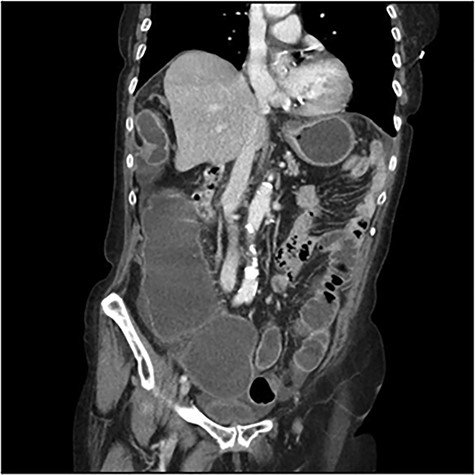

The scanner demonstrated a colonic occlusion resulting from an incarceration, which was diagnosed as a hernia of Bochdalek containing the hepatic angle of the colon (Fig. 2–4).

At the relecture of the images, they showed two old rib fractures. When asked to the patient, she mentioned a past history of a fall 2 years earlier, which directed us to the diagnostic of delayed right diaphragmatic rupture.

CT scan images demonstrating a right diaphragmatic hernia containing intestine.